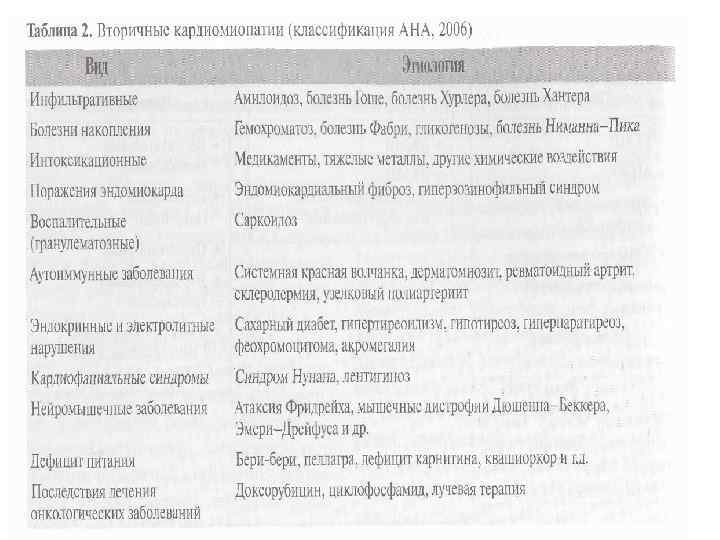

• 2006 год Классификация AHA Дилатационная кардиомиопатия Гипертрофическая кардиомиопатия Рестриктивная кардиомиопатия Аритмогенная кардиомиопатия правого желудочка Неклассифицированные кардиомиопатии

• 2006 год Классификация AHA Дилатационная кардиомиопатия Гипертрофическая кардиомиопатия Рестриктивная кардиомиопатия Аритмогенная кардиомиопатия правого желудочка Неклассифицированные кардиомиопатии